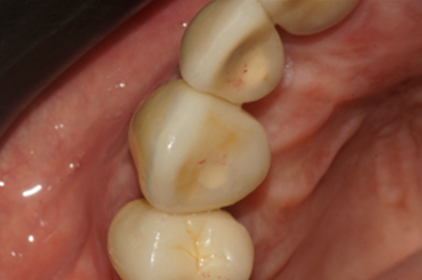

Na segunda consulta, a prótese parafusada metalfree foi instalada e aparafusada a 10 Ncm como recomendado pela fabricante. O orifício de acesso ao parafuso foi restaurado com resina fotopolimerizável e uma radiografia final foi realizada (Figuras 20, 21, 22 e 23).

Figura 20 – Prótese aparafusada torqueada a 10 Ncm

Figura 21 – Imagem da prótese instalada

Figura 22 – Orifício de acesso ao parafuso restaurado